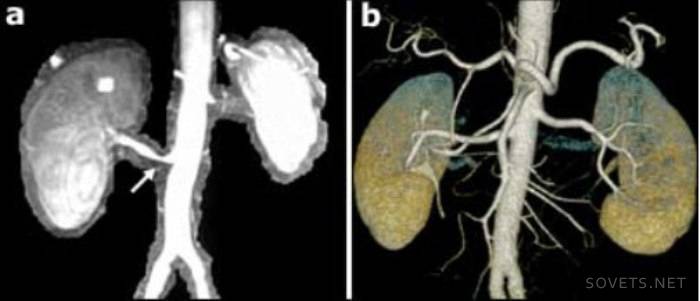

- Obtendo imagens espaciais 3D mais precisas. Modelos tridimensionais mostram com mais precisão a natureza e a localização da patologia. O uso de técnicas de escaneamento em espiral permitiu o uso da angiografia, ou seja, estudo das artérias, para identificar aneurismas vasculares, estreitamento, seu comprimento.

Tomografia renal

Este método do exame dos rins usa-se:

- Para a detecção oportuna de tumores benignos e malignos nos rins, pedras, anormalidades no desenvolvimento dos rins, abcessos, policísticos.

- Para o diagnóstico de lesão renal.

- Uma biópsia renal para monitorar a exatidão da coleta de tecido.

- Após o transplante ou remoção do rim, para monitorar a condição do local operado.

Durante o procedimento, um agente de contraste é usado para melhorar a clareza da imagem. No dia anterior ao exame, o paciente é preparado de acordo com o esquema geralmente aceito.